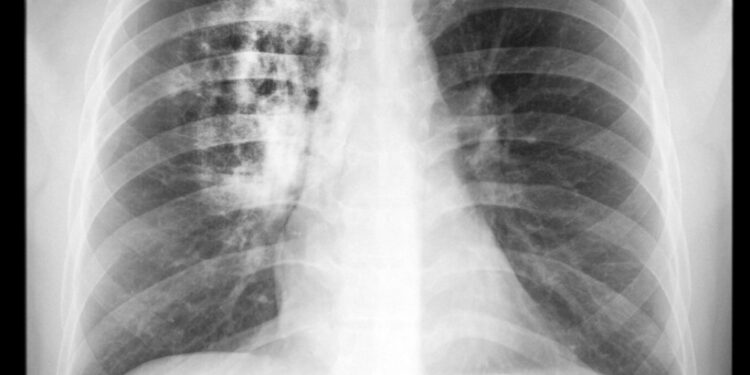

Pancoast auglys – reta plaučių vėžio rūšis, kuri išsivysto viršutinėje plaučio dalyje, pačioje viršūnėje, virš pirmojo šonkaulio. Skirtingai nei daugelis kitų plaučių auglių, Pancoast navikas dažniausiai nesukelia įprastų plaučių ligų simptomų, tokių kaip kosulys ar skausmas krūtinėje. Dėl šios priežasties ligos nustatymas kartais užtrunka, o vėžys gali būti aptinkamas jau išplitęs į aplinkines nervų ar kraujagyslių struktūras.

Ankstyvose stadijose Pancoast navikas sunkiai pastebimas paprastu rentgenu, todėl įtarus ligą dėl būdingų simptomų gydytojas gali skirti sudėtingesnius tyrimus:

Modernios vizualizacijos priemonės, kaip kompiuterinė tomografija, pozitronų emisijos tomografija arba magnetinio rezonanso tyrimas, padeda tiksliau nustatyti naviko vietą, išplitimą ir dydį.